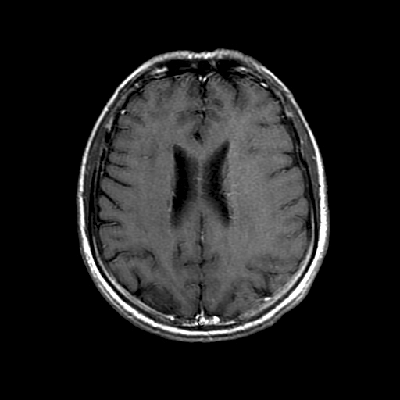

Neurologic and mental examination showed intact immediate memory but inability to recall 3 objects in 5 minutes. He was not oriented to time or space or situation but oriented to person. His remote memory was intact. There was left superior quadrantonopsia but no focal motor or sensory deficits. FLAIR images on MRI showed a lesion in the left mesial temporal lobe (Panel 1). This lesion had increased T2 signal but without enhancement on T1 images. This lesion also had mass-effect and edema within that region. On FLAIR images, there were some small foci of abnormal signal in the white matter of the right parietal lobe (Panel 2) but these foci did not enhance (Panel 3). There is a vague, poorly demarcated, triangular shaped periventricular signal abnormality in the left parietal lobe (Panel 2) but this area did not enhance (Panel 3). On another image (obtained higher to Panel 2 and 3), however, there is a small cluster of enhancing spotty signal in the white matter of the left parietal lobe (Panel 4) and the largest focus is about 0.4 cm in diameter. There were areas with features of encephalomalacia in his right mesial temporal lobe that would be explained by his history of prior infarct.

3. T1+Contrast |